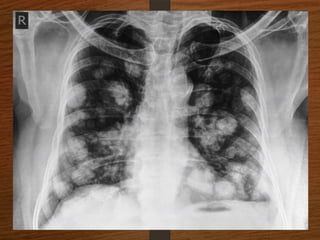

What are the important causes of

cannon ball shadows in chest X-ray?

• Metastasis

• Benign lesion

 Fungal infection—Histoplasmosis, coccidioodomycosis,

aspergillosis.

 Parasitic infection—Filarial infection, hydatid disease.

 Sarcoidosis.

 Wegener’s granulomatosis.

 Rheumatoid nodules.